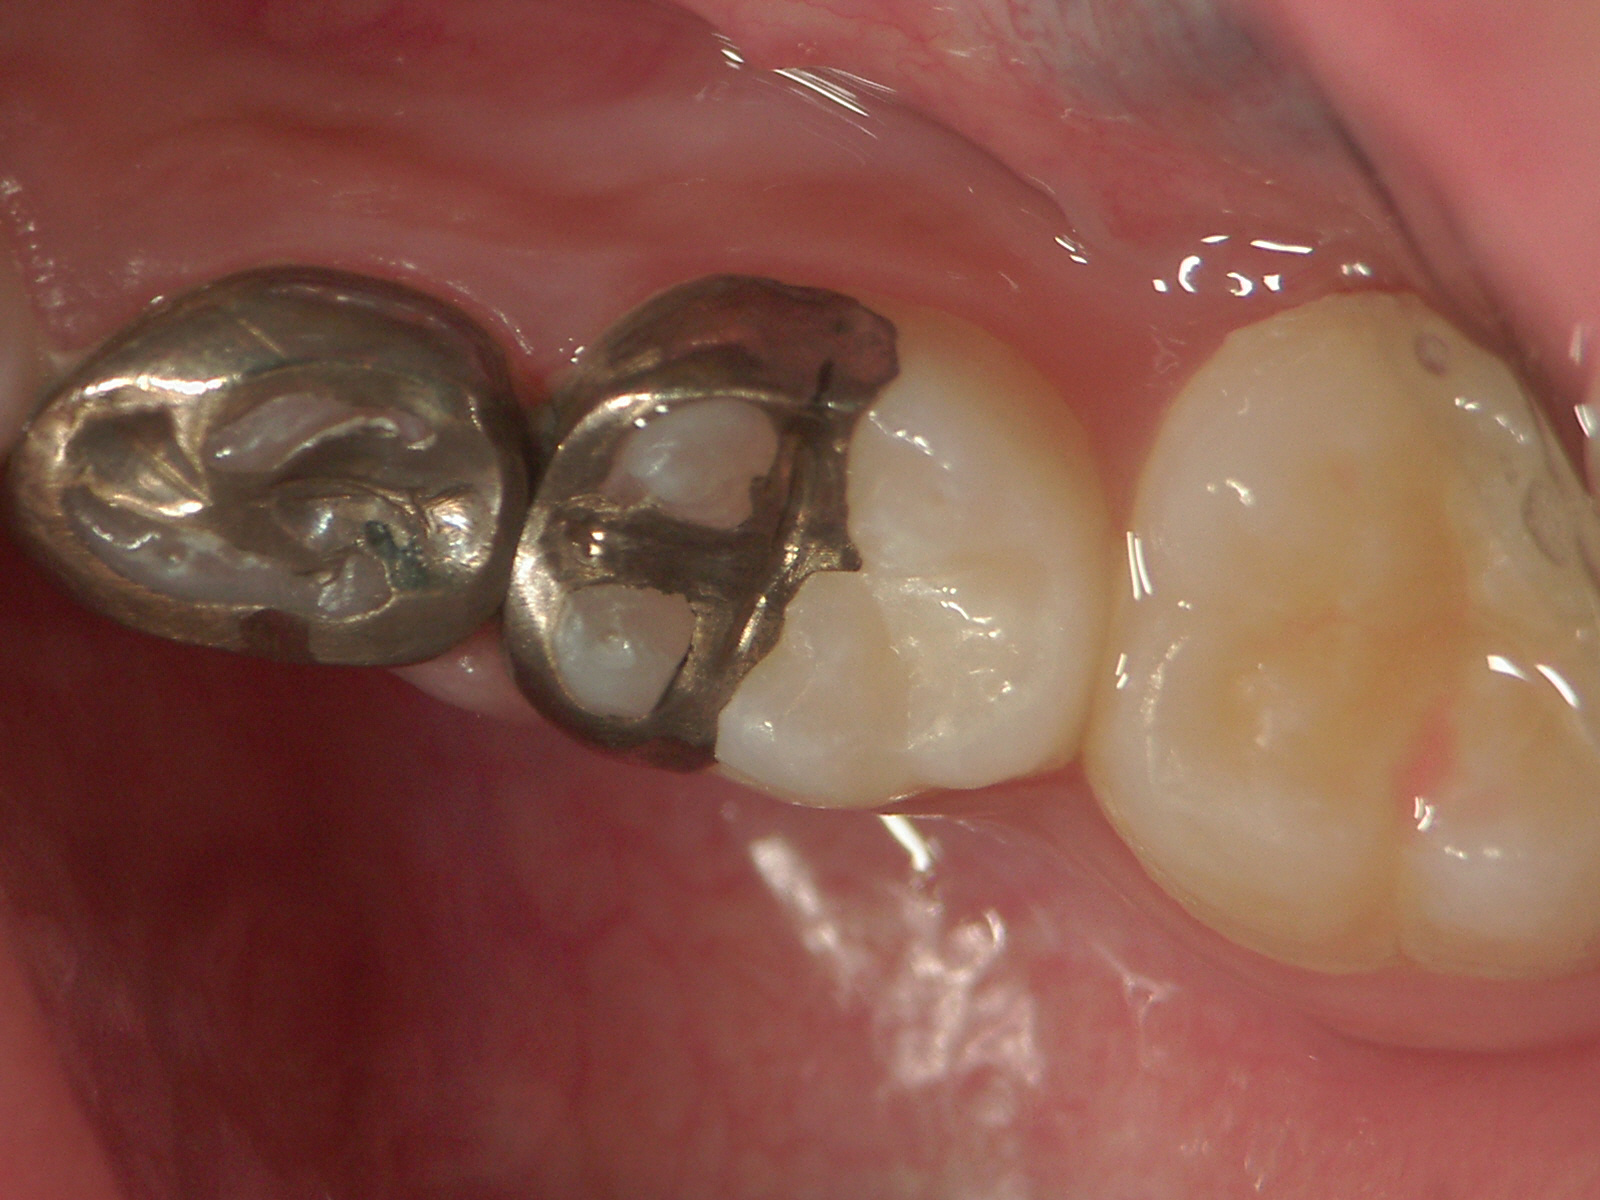

当院では乳歯の奥歯はたいてい右のように銀歯で修復しています。 永久歯に生え換わるまでほとんど

再治療を必要としないからです。 何度も外れると6歳臼歯が手前に移動し、永久歯の生えるスペースをふさいでしまって歯並びが悪くなるからです。 (白いプラスチックの詰め物は外れやすいので隙間の虫歯には使用しません)